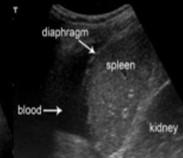

FAST: Estudio de ultrasonido que explora la zona perihepática, pericárdica, periesplénica, peripélvica en busca de la presión de líquido libre en cavidad abdominal (ENARM 2013).

Figura 68. FAST en trauma abdominal

El estudio del paciente con trauma abdominal cerrado e inestabilidad hemodinámica debe realizarse con FAST o lavado peritoneal diagnóstico (ESSALUD 2006)

En caso de inestabilidad hemodinámica, la prioridad es compensarlo reponiendo volumen con cristaloides. El hallazgo positivo en FAST o lavado peritoneal diagnóstico es indicación de laparotomía exploradora, siempre correlacionando con la clínica del paciente.